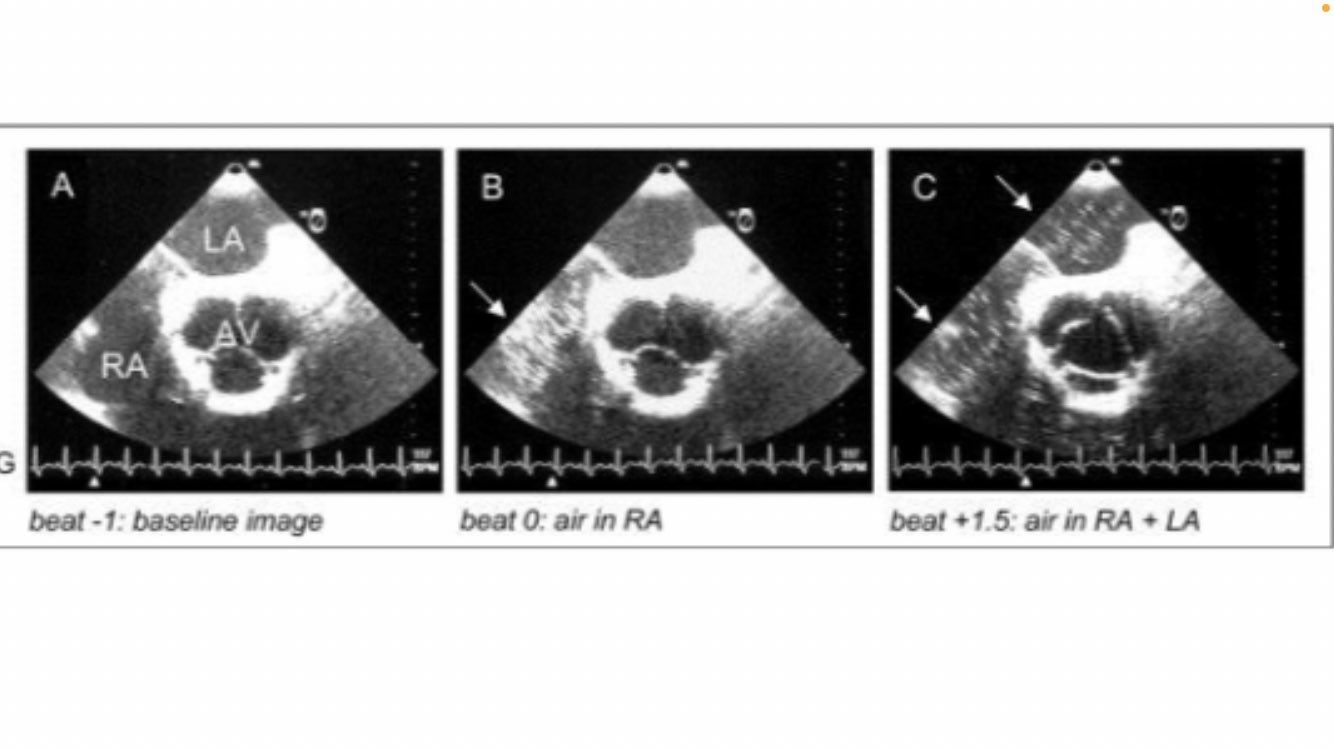

air embolism in right atrium

PFO